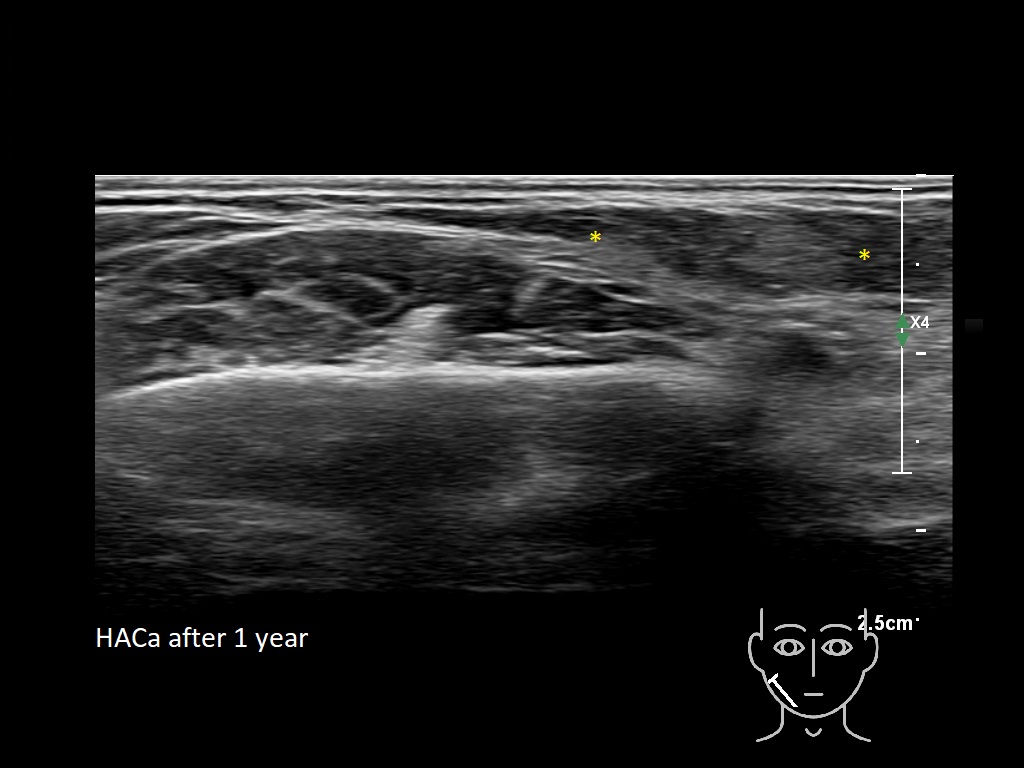

Draw in the image on the right where the fillers are located. To check if your answer is correct, please click on the secondary image.

Draw in the second image below where the fillers are located. To check if your answer is correct, swipe the first image to the right.

HACa 4b e

HACa 5b e

HAca10e